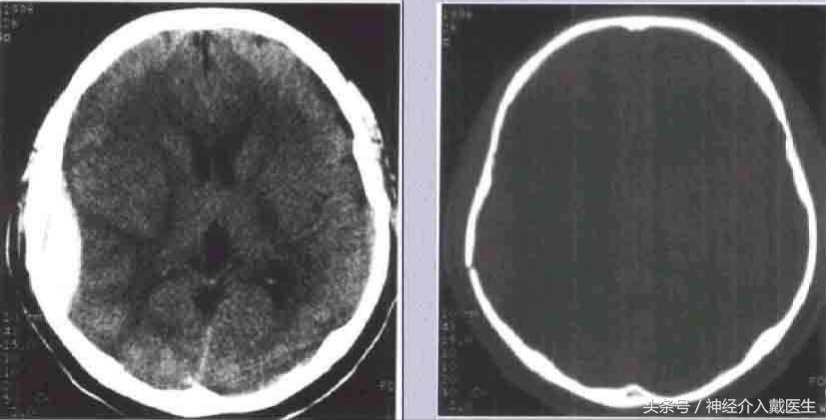

儿童生长性骨折:好发于额顶部,为小儿颅盖线形骨折中的特殊类型,婴幼儿多见。一般认为小儿硬脑膜较薄且与颅骨内板贴附较紧,当颅骨发生骨折裂缝较宽时,硬脑膜亦常同时撕裂、分离,以致局部脑组织、软脑膜及蛛网膜突向骨折的裂隙。由于脑搏动的长期不断冲击,使骨折裂缝逐渐加宽,以致脑组织继续突出,最终形成局部搏动性囊性脑膨出,病儿常伴发癫痛或局限性神经废损。治疗原则以早期手术修补硬脑膜缺损为妥。 凹陷骨折多见于额、顶部,常为接触面较小的钝器打击或头颅碰撞在凸出的物体上所致。着力点头皮往往有擦伤、挫伤或挫裂伤。颅骨大多全层陷入颅内,偶尔仅为内板破裂下凹。一般单纯凹陷骨折,头皮完整,不伴有脑损伤多为闭合性损伤,但粉碎凹陷骨折则常伴有硬脑膜和脑组织损伤,甚至引起颅内出血。

( 1 )闭合性凹陷骨折 儿童较多,尤其是婴幼儿颅骨弹性较好,钝性的致伤物,可引起颅骨凹陷,但头皮完整无损,类似乒乓球样凹陷,亦元明显的骨折线可见。患儿多无神经机能障碍,无需手术治疗。如果凹陷区较大较深,或有脑受压症状和体征时,可于凹陷旁钻孔,小心经硬膜外放入骨撬,将陷入之骨片撬起复位。术后应密切视察以防出血。

成年人单纯凹陷骨折,如果面积大于 5cm,或者直径,深度超过 lcm ,或者伴有神经缺损症状和体征,需要手术治疗。

( 2 开放性凹陷骨折 常系强大之打击或高处坠落在有突出楞角的物体 所致,往往头皮、颅骨、硬脑膜与脑均同时受累,而引起的开放性颅脑损伤。临床所见开放性凹陷骨折有洞形骨折及粉碎凹陷骨折两种常见类型。临床表现常以局部神经缺损为主。治疗原则是尽早施行颅脑清创缝合术,变开放伤为闭合伤,防止感染,减少并发症与后遗症。 粉碎凹陷骨折:即粉碎性骨折伴有着力部骨片凹陷,常为接触区较大的重物致伤,不仅局部颅骨凹曲变形明显,引起陷入,同时,颅骨整体变形亦较大,造成多数以着力点为中心的放射状骨折。硬脑膜常为骨碎片所刺破,偶尔亦有硬脑膜完整者,不过脑损伤均较严重,除局部有冲击伤之外,常有对冲性脑挫裂伤或颅内血肿,治疗方法与洞形骨折相似。